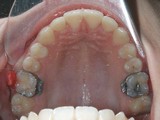

Zkřížený skus, předkus, nedostatek místa pro špičák. Léčba pomocí aparátu Hyrax a dále fixními aparáty v obou čelistech s jumping aparátem. V ústech přítomné MARA-stopy na dočasnou stabilizaci výsledku.

Před léčbou        Po léčbě

horní pac2       horní pac2